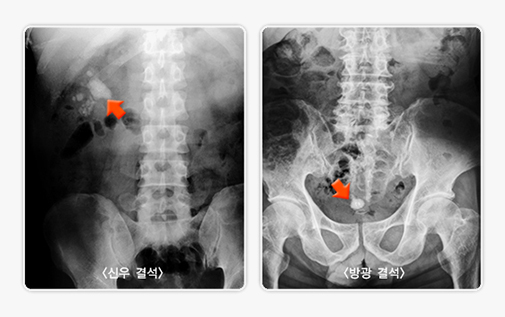

• 복부 방사선 촬영 복부의 X선 사진으로 대부분의 신장에 생긴 결석을 발견할 수 있으며 신장 결석의 위치와 크기를 알 수 있습니다. 그러나 일부 특정한 성분(요산)으로 구성된 결석은 방사선을 투과시키므로 방사선 검사에서 발견이 되지 않을 수 있습니다.

복부 방사선 촬영에서 발견된 신장 결석